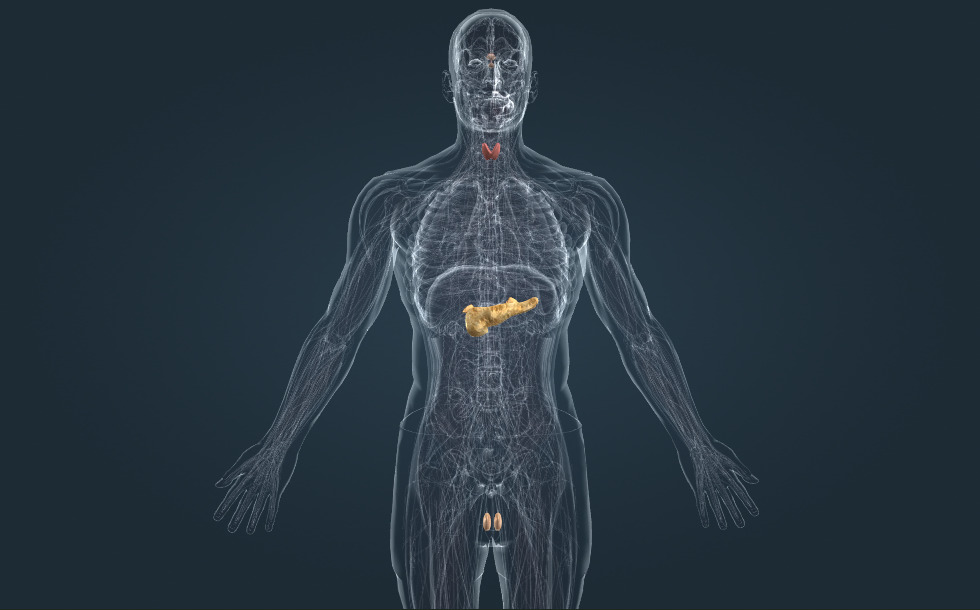

Hormonaal stelsel

- bijschildklieren - Ze scheiden het parathormoon uit dat de calciumconcentratie in het bloed verhoogt. Calcitonine, wat afgescheiden wordt door de schildklier, heeft het tegenovergestelde effect: het verlaagt de calciumconcentratie in het bloed.

- bijnier - Bestaat uit een cortex en het hersenmerg. De cortex scheidt hormonen die het sodium- en glucoseniveau in het bloed verhogen. Het hersenmerg produceert epinefrine (adrenaline), een stresshormoon dat een belangrijke rol speelt bij de acute stressreactie.

- testikel - Het produceert sperma en het hormoon testosteron (mannelijk geslachtshormoon), wat de rijping van sperma en de ontwikkeling van een mannelijk figuur en lichaamsbeharing stimuleert.

- alvleesklier - Scheidt insuline af, een hormoon dat het glucoseniveau in het bloed verlaagt. Een tekort aan glucose veroorzaakt diabetes.

- schildklier - Scheidt de schildklierhormonen af die de biologische oxidatie stimuleren. Ze speelt een belangrijke rol bij de normale ontwikkeling van de hersenen en groei. Een overmatige productie van de schildklierhormonen veroorzaakt de ziekte van Graves, terwijl hypothyreoïdie schildkliervergroting veroorzaakt.

- hypofyse - Vormt samen met de hypothalamus de hypothalamus-hypofyse-as, het centrum van ons hormonaal stelsel.

Hormonen worden geproduceerd door de klieren van het endocrien stelsel. Adrenaline wordt afgescheiden door de bijnier, insuline door de alvleesklier en thyroxine door de schildklier.

Het centrum van het endocrien stelsel is de hypothalamus-hypofyse-as. De hypothalamus produceert hormonen die de hypofyse reguleren, waar ze de productie van andere hormonen stimuleert. Deze hormonen stimuleren andere endocriene klieren zoals de schildklier, de bijnier en de reproductieve klieren. De alvleesklier wordt niet gereguleerd door de hypothalamus-hypofyse-as.

Hormonen worden geproduceerd door de klieren van het endocrien stelsel. Adrenaline wordt afgescheiden door de bijnier, insuline door de alvleesklier en thyroxine door de schildklier.

Het centrum van het endocrien stelsel is de hypothalamus-hypofyse-as. De hypothalamus produceert hormonen die de hypofyse reguleren, waar ze de productie van andere hormonen stimuleert. Deze hormonen stimuleren andere endocriene klieren zoals de schildklier, de bijnier en de reproductieve klieren. De alvleesklier wordt niet gereguleerd door de hypothalamus-hypofyse-as.